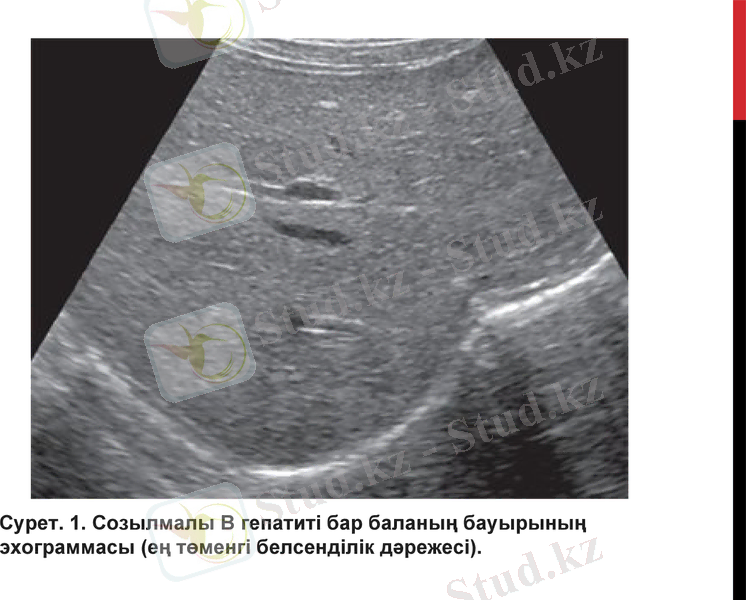

Сурет. 1. Созылмалы В гепатиті бар баланың бауырының эхограммасы (ең төменгі белсенділік дәрежесі) .